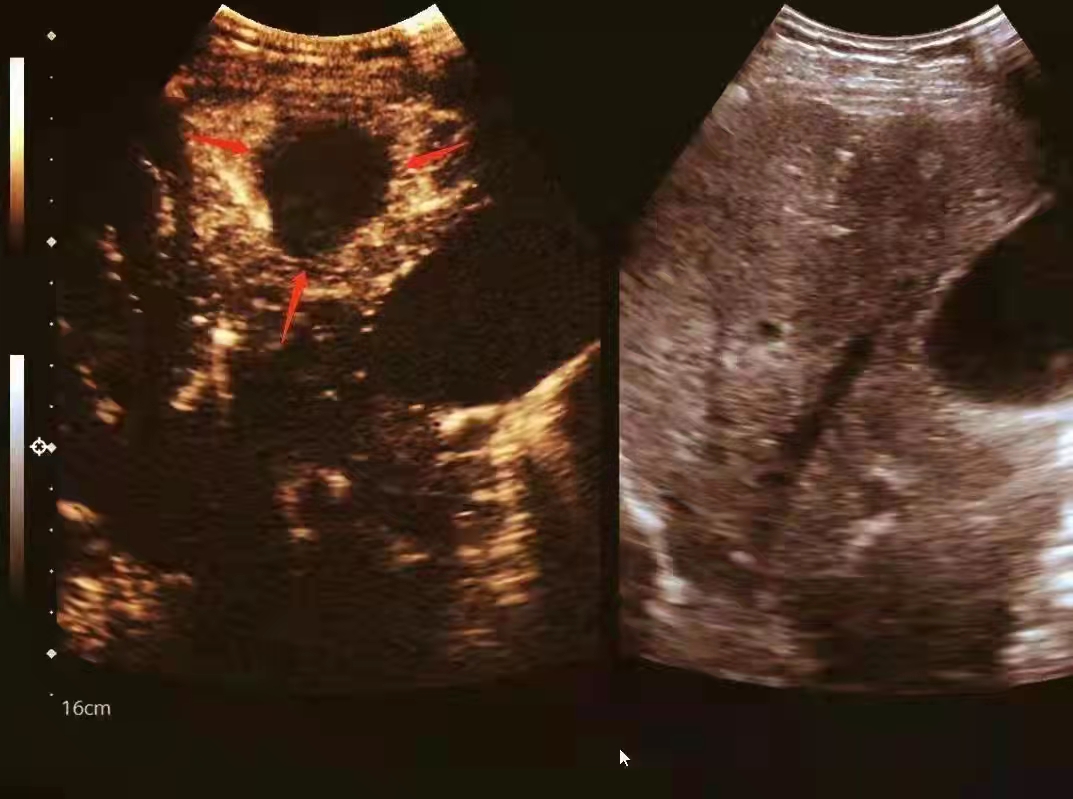

近日,消化内科、超声科联手为束大哥进行手术,在超声引导下精确进入肿瘤内部,针尖到达肿瘤的远端边缘开始消融,根据消融产生的气化情况缓慢退针,将肿块最大程度消融失活。10分钟后,患者大小为2.0cmx 1.8cm单发肿瘤病灶被消融完整,而皮肤仅留下不足3mm的针眼,用一个止血贴就可以覆盖。手术顺利完成,束大哥无明显不适感觉。

超声介入引导的肿瘤消融手术是使用高强度聚焦超声消融治疗设备治疗各类实体良恶性肿瘤(如肝癌、骨肿瘤、乳腺癌、胰腺癌、子宫肌瘤)的一种治疗方法,相对于传统手术有费用低,损伤小,痛苦小,恢复快等诸多优势。“国际诊疗指南显示,早期肝癌单发直径小于等于5厘米,或肿瘤个数3个以内的,最大不超过3厘米,且无门静脉癌栓或肝外转移,可以使用微创消融治疗。”该院消化内科主任唐敏说。

超声科主任詹小林介绍,该微创治疗技术整个治疗过程无创伤、不出血,真正实现从体外治疗体内的肿瘤,杀灭肿瘤组织。治疗时采用:点-线-面-体的组合扫描方式,对整个肿瘤进行适形消融。对于胃癌及肠癌患者常伴有肝转移灶,如果符合指征,及时做好微创消融手术可以取得一样的效果。(朱丽丽)